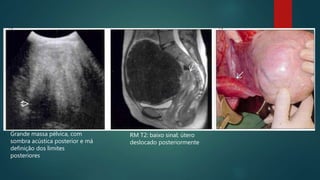

Grande massa pélvica, com

sombra acústica posterior e má

definição dos limites

posteriores

RM T2: baixo sinal; útero

deslocado posteriormente